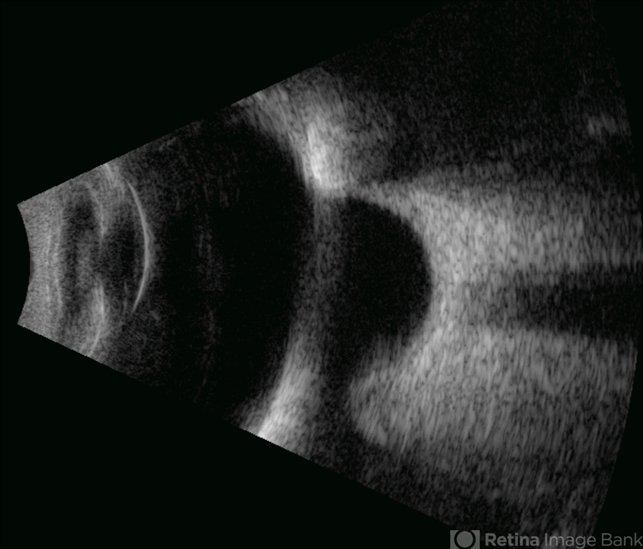

- scleral buckle

- Gustavo U. Fonseca Aguirre, Hospital Conde de Valenciana, Ciudad de México

- Ultrasonography device

- This B-mode axial ultrasound scan shows an eye with a scleral buckle in place for previous rhegmatogenous retinal detachment. The image demonstrates the characteristic indentation of the ocular wall at the buckle site, with proper retinal reattachment.